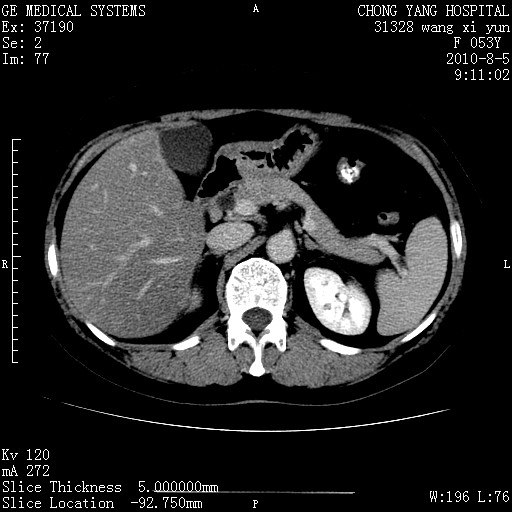

标题: CT28214:F41Y 血尿二十天,建议盆腔平扫加增强。

胆管细胞ca?

1)考虑肝左叶胆管细胞癌。2)脂肪肝。

支持胆管细胞ca。